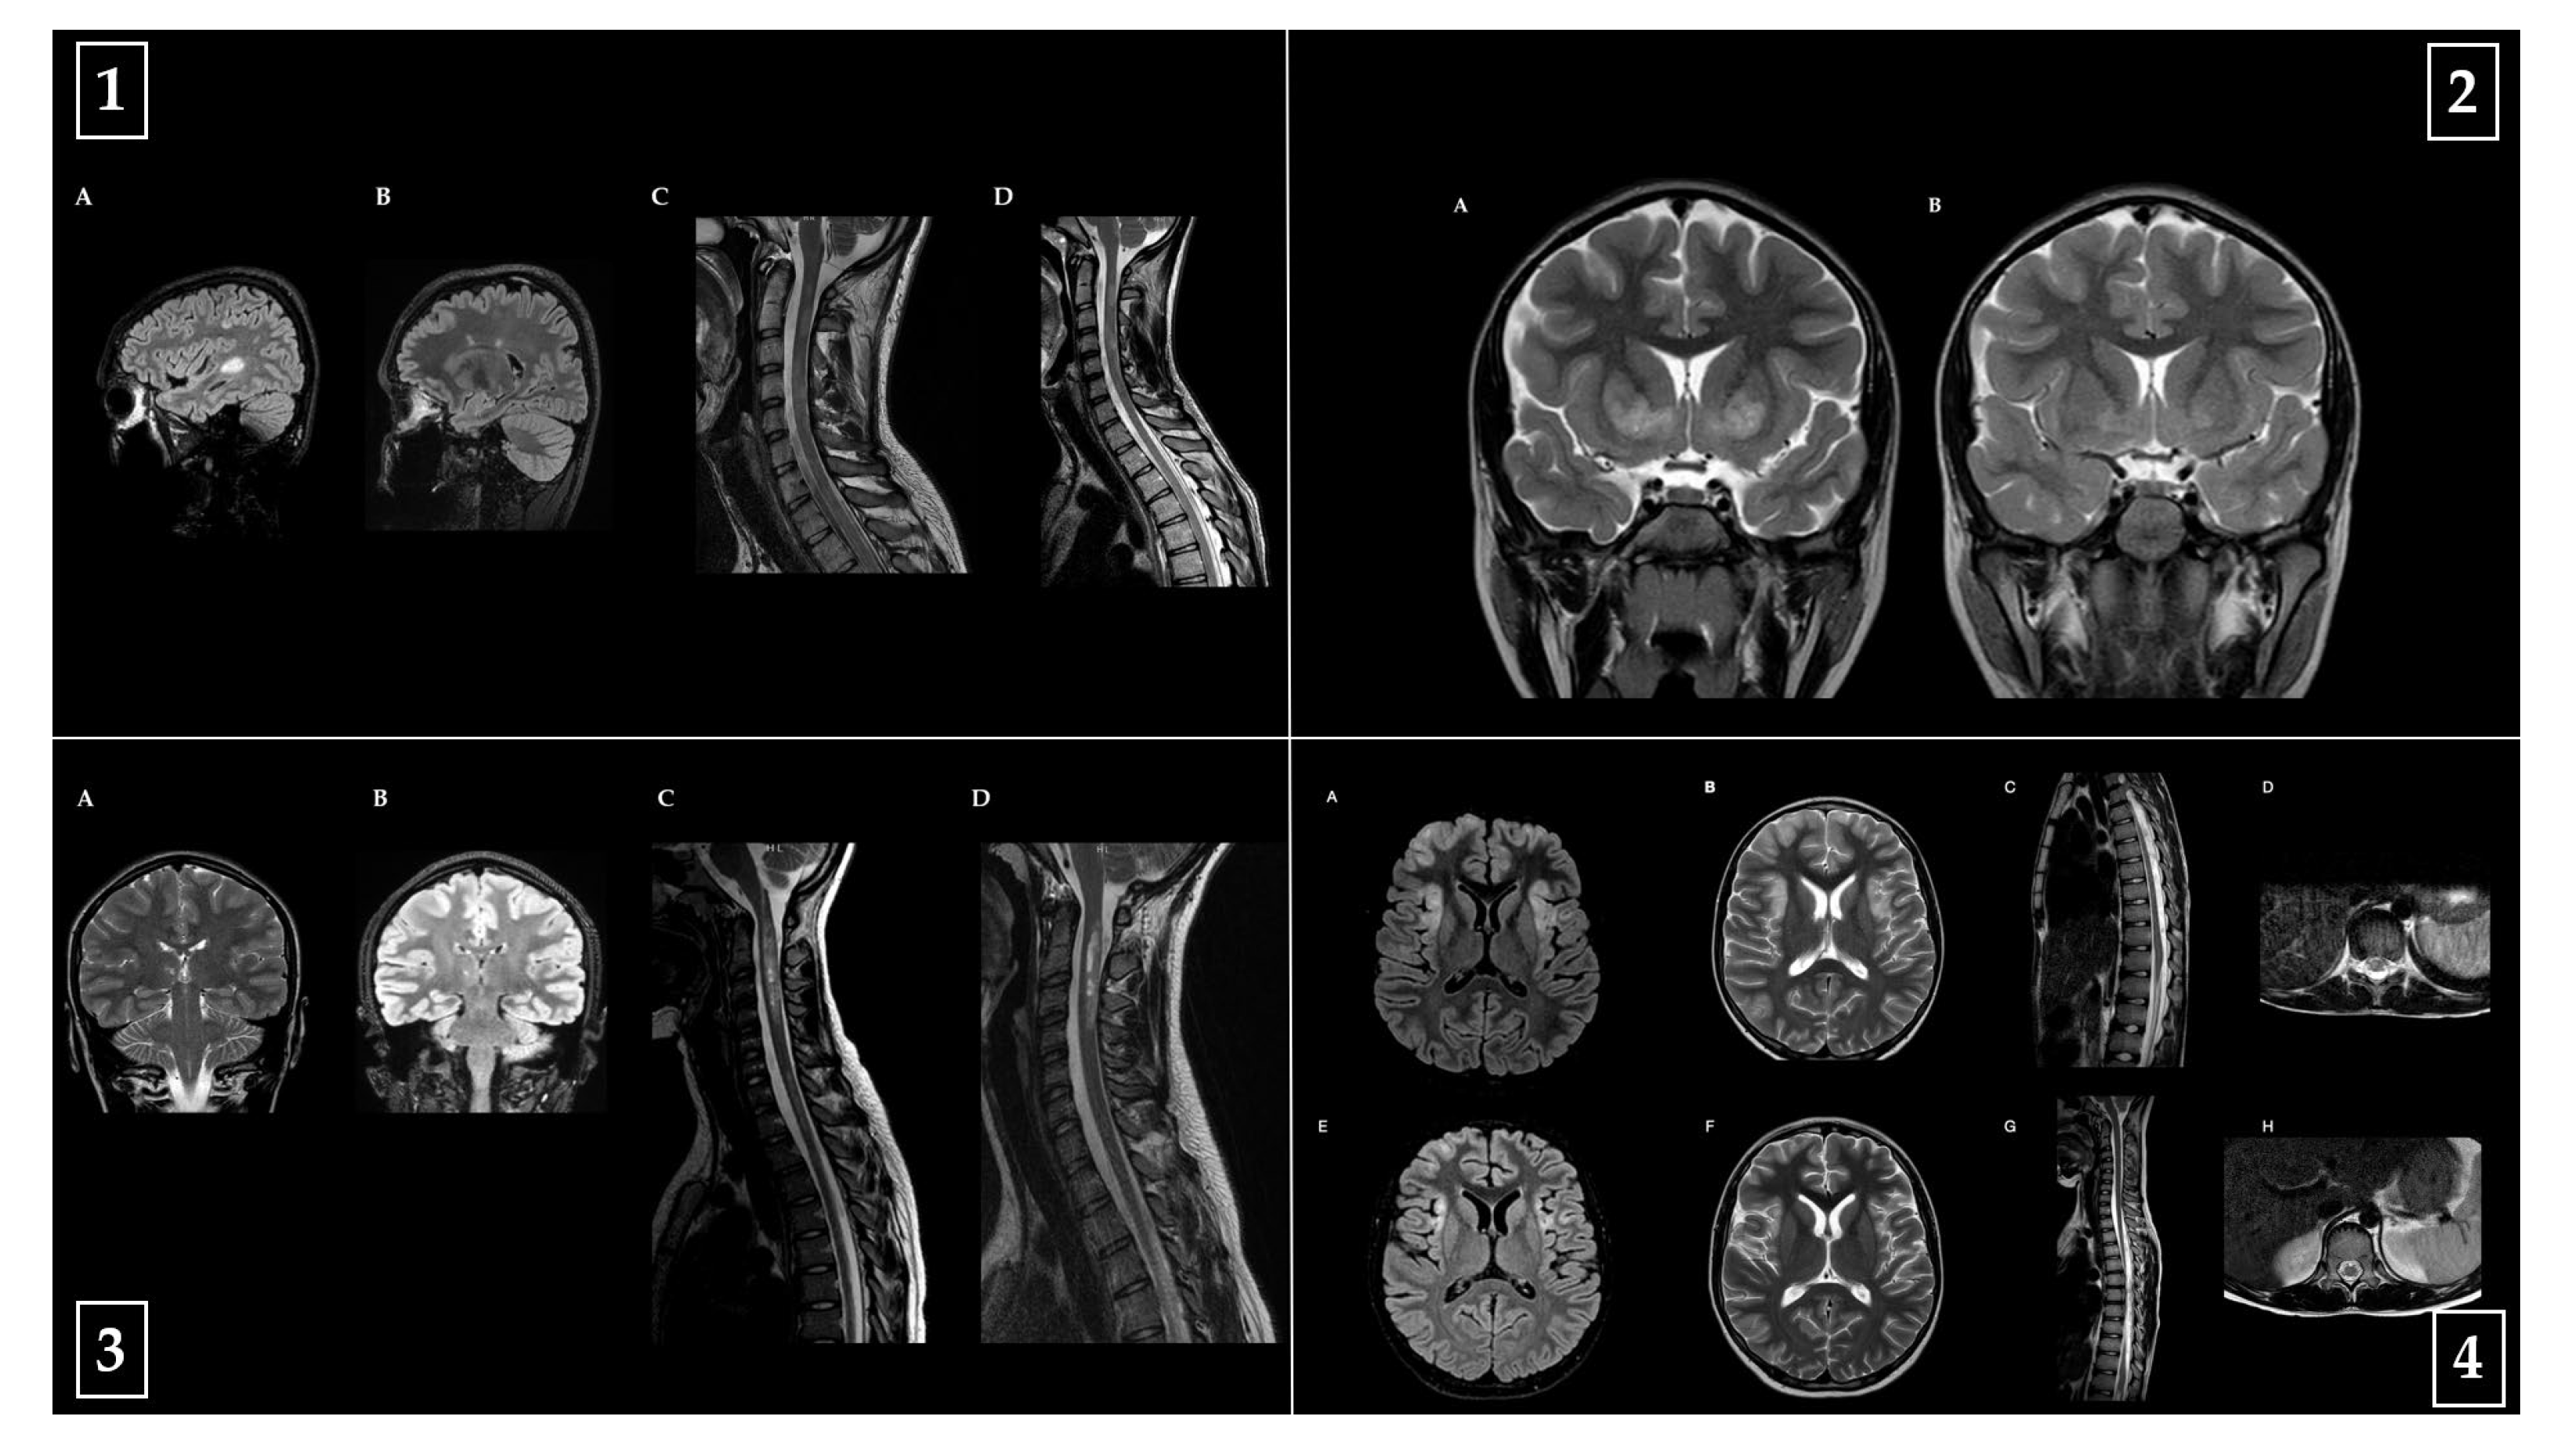

Representative baseline and follow-up MRI images from one patient per diagnostic category (MS, MOGAD, NMOSD, ADEM) are shown in Figure 5, highlighting key radiological features and their evolution over time.

Figure 5. Representative brain and spinal cord MRI findings from four pediatric patients with distinct acquired demyelinating disorders of the central nervous system. All images include acute-phase and follow-up studies. (1) Multiple sclerosis (MS): MRI of an 18-year-old male patient with a diagnosis of MS. (A,C) Acute phase: sagittal FLAIR brain MRI (A) demonstrates multiple hyperintense lesions in supratentorial and infratentorial regions, including the left temporal peritrigonal white matter and brainstem, with incomplete ring enhancement of the temporal lesion. Sagittal T2-weighted cervical spinal MRI (C) reveals extensive intramedullary hyperintensities from C2 to C6, predominantly involving the posterior columns, with marginal ring enhancement at C4–C5. A separate lesion is noted in the left lateral cord at D10–D11. (B,D) Follow-up imaging: brain MRI (B) shows stable lesion burden without new enhancement, while cervicodorsal MRI (D) confirms persistence of spinal lesions without new findings. (2) Acute disseminated encephalomyelitis (ADEM): MRI of a 5-year-old female patient with a diagnosis of ADEM. (A) Coronal T2-weighted brain MRI during the acute phase shows bilateral and symmetrical hyperintense lesions involving the basal ganglia (caudate heads and anterior pallido-putaminal regions), tegmentum, periaqueductal and hypothalamic periventricular gray matter, and optic tracts. Moderate enlargement of the convexity subarachnoid spaces and thinning of the mid-posterior corpus callosum are also evident. (B) At follow-up, a faint residual hyperintensity persists in the globi pallidi, with reduced ventricular and subarachnoid space enlargement. No contrast enhancement is observed at either timepoint. (3) Neuromyelitis optica spectrum disorder (NMOSD): MRI of a 16-year-old female patient with a diagnosis of NMOSD. (A,C) Acute phase: coronal T2-weighted brain MRI (A) shows a faint lesion in the dorsal medulla near the area postrema and a focal lesion in the right ventro-thalamic region. Sagittal T2-weighted spinal MRI (C) reveals a longitudinally extensive lesion from the cervicomedullary junction to C4, with cord swelling, bright spotty lesions, and intense posterior nodular enhancement. A thoracic lesion is visible at D5–D6, with subpial serpiginous enhancement. (B,D) Follow-up imaging: brain MRI (B) shows persistence of the right thalamic lesion without new abnormalities; spinal MRI (D) reveals reduced lesion length and residual pseudocystic and nodular components, particularly in the posterior cord at C2–C4 and dorsolateral thoracic cord at D5–D6. (4) MOG antibody-associated disease (MOGAD): MRI of a 13-year-old male patient with a diagnosis of MOGAD. (AD) Acute phase: axial FLAIR (A) and T2-weighted (B) brain MRI demonstrate bilateral multifocal lesions in the cortical and subcortical regions of the temporal, insular, and frontal lobes. Sagittal (C) and axial (D) T2-weighted spinal MRI shows a linear hyperintense lesion affecting the conus medullaris. (EH) Follow-up imaging shows partial resolution of cerebral lesions on FLAIR (E) and T2 (F) and complete resolution of spinal abnormalities in both sagittal (G) and axial (H) views.